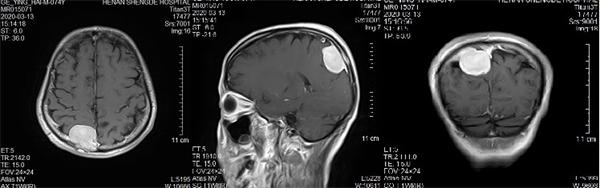

映象网信阳讯(记者 吴彦飞 通讯员 吴琼 曹启合)日前,74岁的葛大爷,因“发作性头晕5年”,在居住当地医院行颅脑MRI(核磁共振)提示颅内占位。紧急转入河南圣德医院神经外科,行MRI提示:矢状窦旁脑膜瘤。

入院后河南圣德医院副院长兼神经外科主任于耀宇查看患者病情,告知其家属脑肿瘤直径较大,压迫功能区,且与上矢状窦粘连,占位效应明显,有明确手术指征,但手术风险较大,手术过程有可能造成上矢状窦大出血及部分神经功能缺失,家属商量后同意手术。

术前核磁共振检查